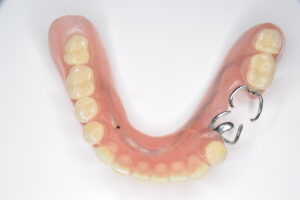

まず、保険のクラスプ義歯がどのような構造かをおさらいします。一般的なクラスプ義歯は、残っている歯に「クラスプ」と呼ばれる金属のバネを引っ掛けて入れ歯を支えます。

抜けた歯を補うために、歯ぐきと同色のプラスチックに人工の歯をつけ、その横に金属のクラスプが付く、という形です。

問題は、クラスプが歯にただ引っ掛けられているだけのため、硬いものを噛むと多少のがたつきが起こり、横からのねじれに弱い点です。

その結果、食べ物が挟まりやすく、噛むたびに支えている歯が揺さぶられます。入れ歯を外すときにも歯がさまざまな方向に揺れるため、歯に負担がかかるのです。

クラスプ義歯はこれらを満たす構造ですが、クラスプの形状ゆえに横揺れが生じ、支えている歯に負担を与えやすいのです。